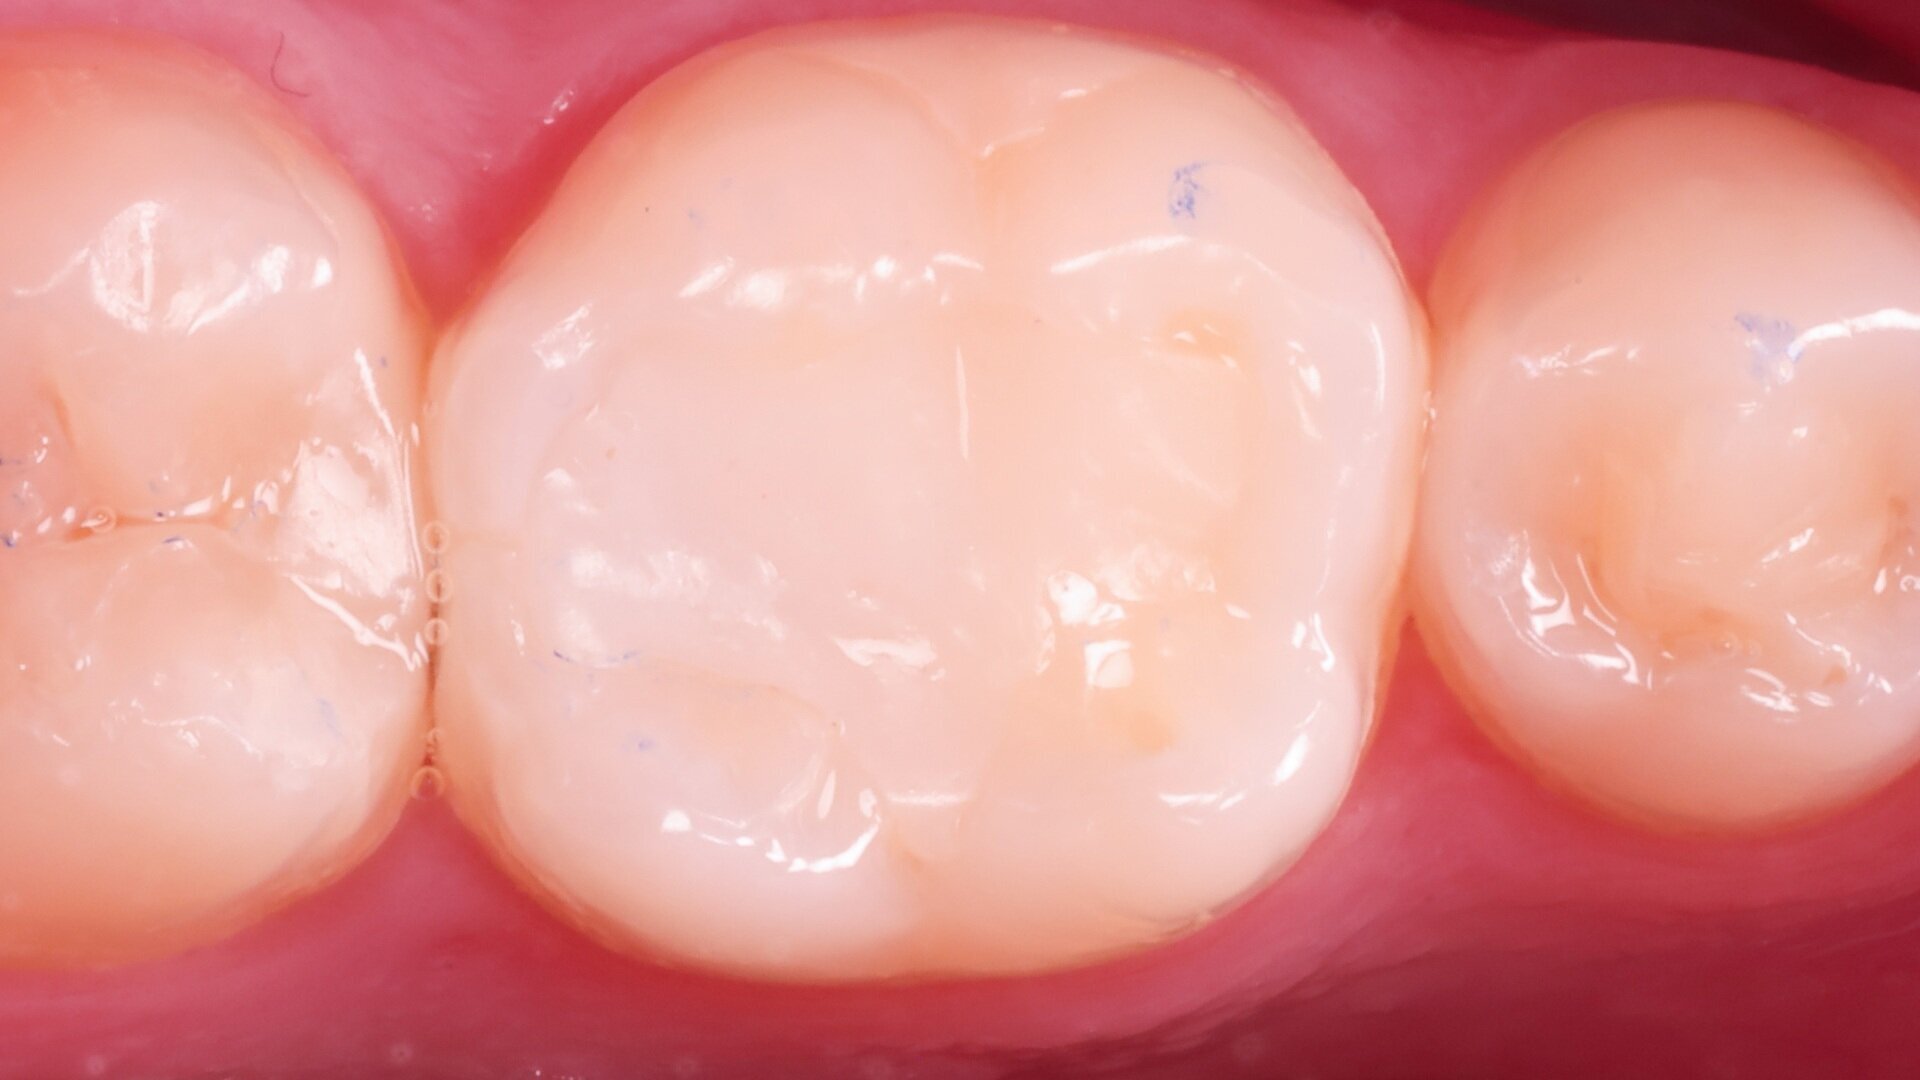

Fig. 2: Panoramic radiograph showing a distal carious lesion.

Treatment focused on a mandibular first molar with existing Class I and V composite restorations (Fig. 1). The tooth was asymptomatic, and cold testing revealed a normal response. A distal carious lesion, which was not clinically visible, was first suspected during routine screening and its extent clearly identified on the panoramic radiograph (Fig. 2).